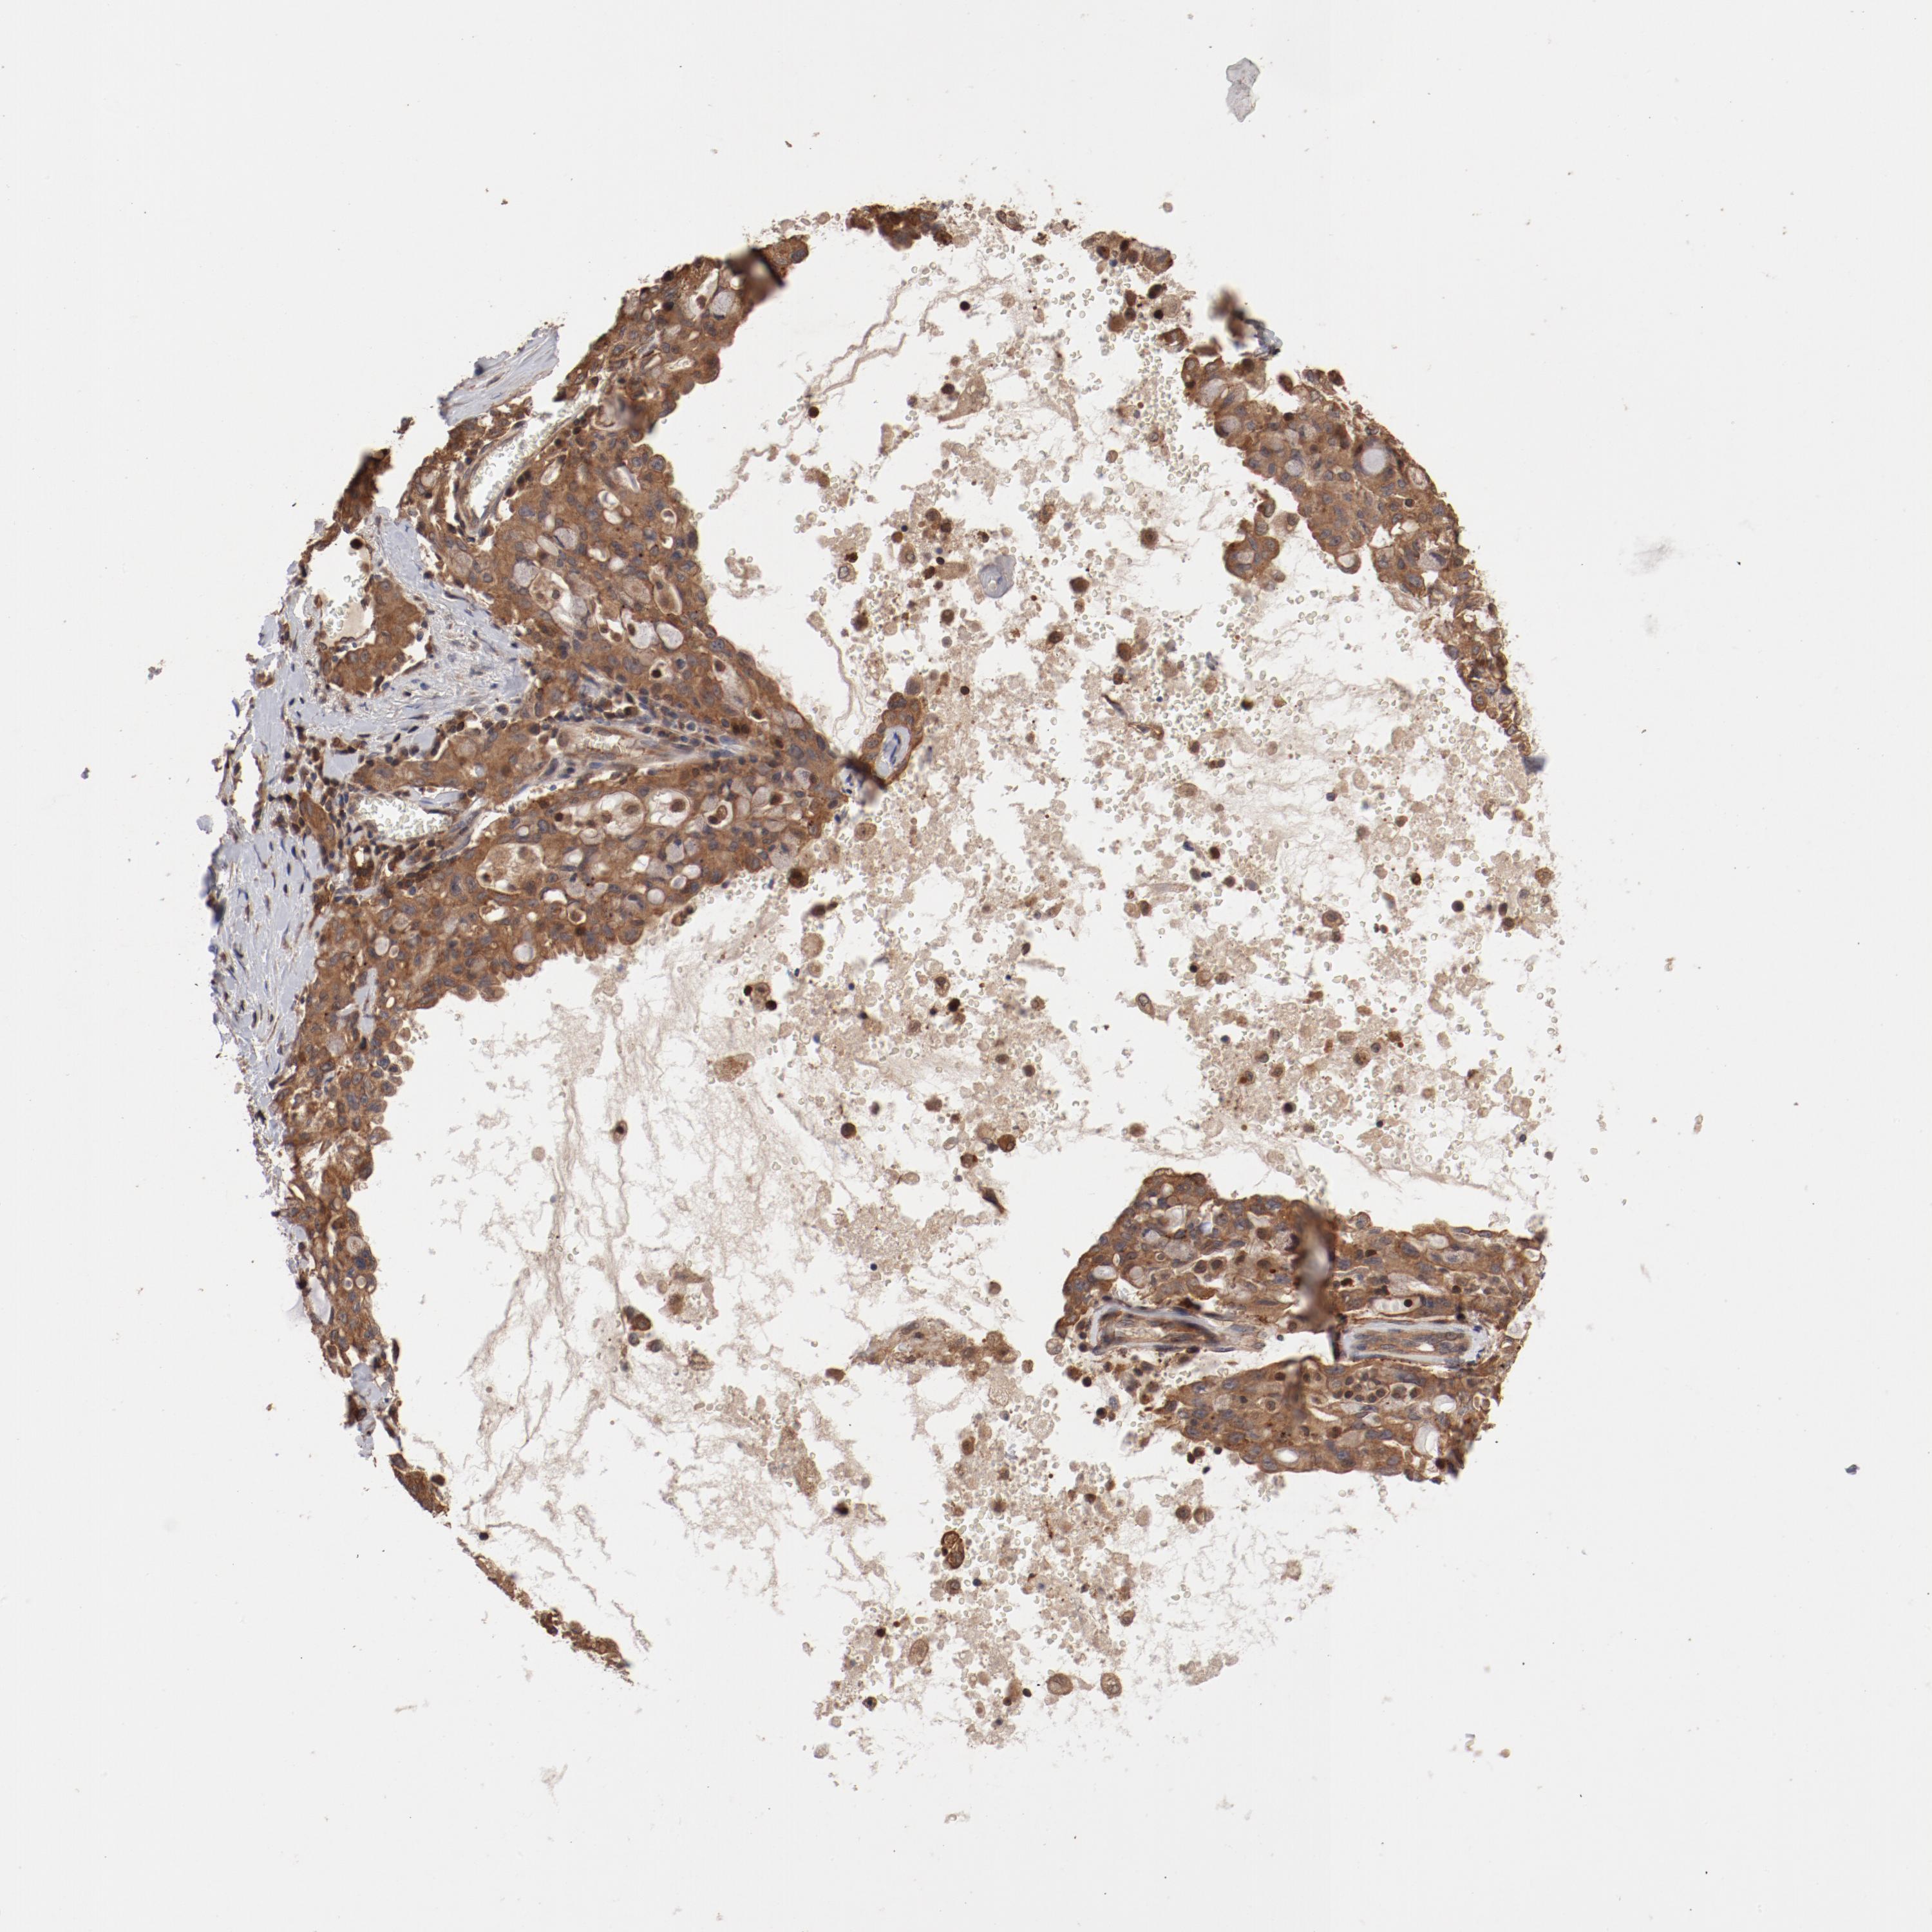

LUNG ADENOCARCINOMA (VALIDATION) - Interactive survival scatter ploti

The Survival Scatter plot shows the clinical status (i.e. dead or alive) for all individuals in the patient cohort, based on the same data that underlies the corresponding Kaplan-Meier plots. Patients that are alive at last time for follow-up are shown in blue and patients who have died during the study are shown in red.

The x-axis shows the expression levels (FPKM) of the investigated gene in the tumor tissue at the time of diagnosis. The y-axis shows the follow-up time after diagnosis (years). Both axes are complimented with kernel density curves demonstrating the data density over the axes. The top density plot shows the expression levels (FPKM) distribution among dead (red) and alive patients (blue). The right density plot shows the data density of the survived years of dead patients with high and low expression levels respectively, stratified using the cutoff indicated by the vertical dashed line through the Survival Scatter plot. This cutoff is automatically defined based on the FPKM cutoff that minimizes the p-score. The cutoff can be changed by dragging the vertical line or by entering a cutoff value in the square labeled "Current cut-off".

Under the Survival Scatter plot the p-score landscape (black curve; left axis) is shown together with dead median separation (red curve; right axis). Dead median separation is the difference in median mRNA expression between patients who have died with high and low expression, respectively. It is calculated as follows: median FPKM expression of dead patients with high expression - median FPKM expression of dead patients with low expression. This is intended to aid the user in visually exploring custom cutoffs and the associated p-scores and dead median separation.

Individual patient data is displayed and can be filtered by clicking on one or more of the category buttons on the top of the page. Categories describing expression level and patient information include: high, low, alive, dead, female, male and tumor stages. The scale of the x-axis can be toggled between linear and log-scale by clicking on the "x log" button. Mouse-over function shows TCGA ID, patient information and mRNA expression (FPKM) for each patient.

& Survival analysisi

Kaplan-Meier plots summarize results from analysis of correlation between mRNA expression level and patient survival. Patients were divided based on level of expression into one of the two groups "low" (under cut off) or "high" (over cut off). X-axis shows time for survival (years) and y-axis shows the probability of survival, where 1.0 corresponds to 100 percent.

GUF1 is not prognostic in Lung Adenocarcinoma (validation)

: 9.75